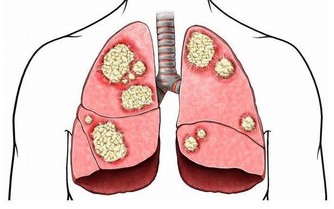

其實,不使用公筷是給細菌,尤其是幽門螺桿菌創造了傳播途徑。

幽門螺桿菌主要潛伏在胃粘膜組織中,人一旦感染這種細菌,就可能引起口臭、胃炎,甚至是胃癌。